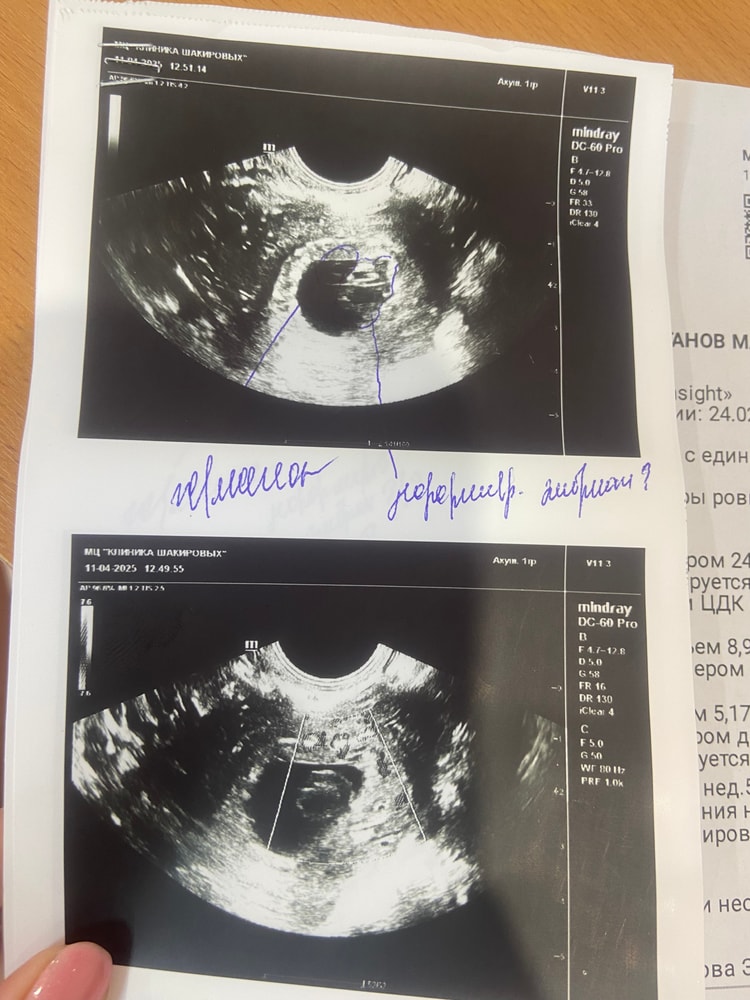

Марина, вот 7 апреля на первом узи у меня пя 12,98mm. И 11 марта я была на втором узи, я у узиста спросила, мне ставят срок 6 недель, это акушерские? Она мне ответила, что нет эмбриональные. Уже не знаю кого слушать и что делать

У меня в феврале была похожая история, ждала до 8-9 недель, но положили в больницу под наблюдение пролежала до ПЯ 28,8мм тм стал уменьшатся 1,8 мм а по первом узи 2,5мм потом 2 мм, подписала согласие на вакуум, так как самой стало видно что уже ждать бессмысленно, попробуйте уговорить врача положить под наблюдение так как сроки позволяют, хгч неинформативно уже, у меня отлично рос как обычная Б, но с первого узи ставили под вопросом, и так все 4 узи подтверждали анэмбрионию, не теряйте надежду но готовьтесь к худшему что бы быть готовой к любому исходу. Первое узи пя 9,3 мм жм 2,5мм 4459хгч Второе узи пя 21мм жм 2,5мм 8135хгч (в платной клинике ) Третье узи пя 25мм жм 2мм Четвертое узи пя 28,8 жм 1,8мм подтвердили Анэмбрионию подпись на вакуум хгч 18709 ( в стационаре )

Я бы переделала узи, раз рост хгч такой шикарный и такие данные узи, действительно пугает что нашли еще что-то, КРОМЕ эмбриона и жм , +25мм пустое пя тоже вызывает сомнения

hsnvnst, жм есть

Диана Ноилес, да, я вижу. Жм вообще до 15мм пя появляется, а эмбрион ждут до 25мм. У вас уже срок поджимает(

Не хочу пугать, но учитывая что в плодном яйце врач видит что-то странное без кровотока и учитывая какой у вас быстрый рост ХГЧ при отсутствии эмбриона, то пузырный занос может быть вариантом тоже. В любом случае, идите к хорошему УЗИсту. Удачи!

Если сомневаетесь, сделайте через неделю, 1,5 ещё раз узи.. Может сердцебиение появится.. Хотя если деформированный эмбрион... (1ый раз о таком слышу если честно), Хотя тут не знаешь что вам посоветовать... Наверное всё таки слушать врачей.. Я бы через неделю сделала узи и там решала...